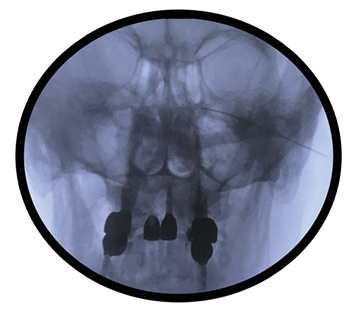

Figura 1

Figura 2